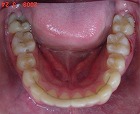

矯正後

s-090324 upper teeth cut.jpg

s-090324 lower teeth cut.jpg